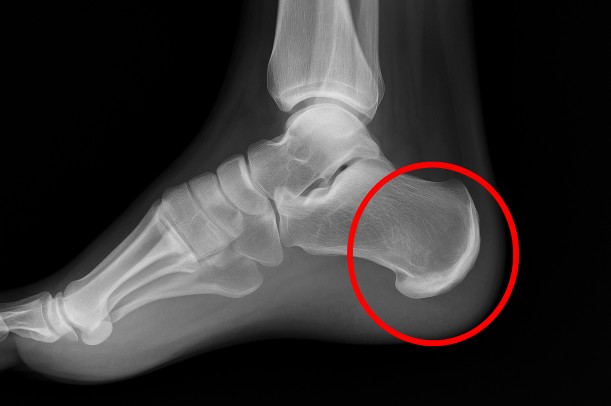

必要に応じて、レントゲンや超音波検査が行われることもあります。

レントゲンでは骨端線の変化や、骨の一部に炎症や剥離がないかを確認する目的で使われることが多いようです。

超音波(エコー)では軟部組織の状態をリアルタイムで見られるため、炎症の有無を把握しやすいとも言われています。

これらの検査を通して、疲労骨折やアキレス腱炎など、似た症状の別疾患と区別することができます。

シーバー病と似た症状を示す病気としては、「踵骨骨挫傷(しょうこつこつざしょう)」や「足底筋膜炎」などがあります。これらは痛みの位置や発症のきっかけが異なるため、触診や画像検査によって慎重に見分けることが大切だと言われています。